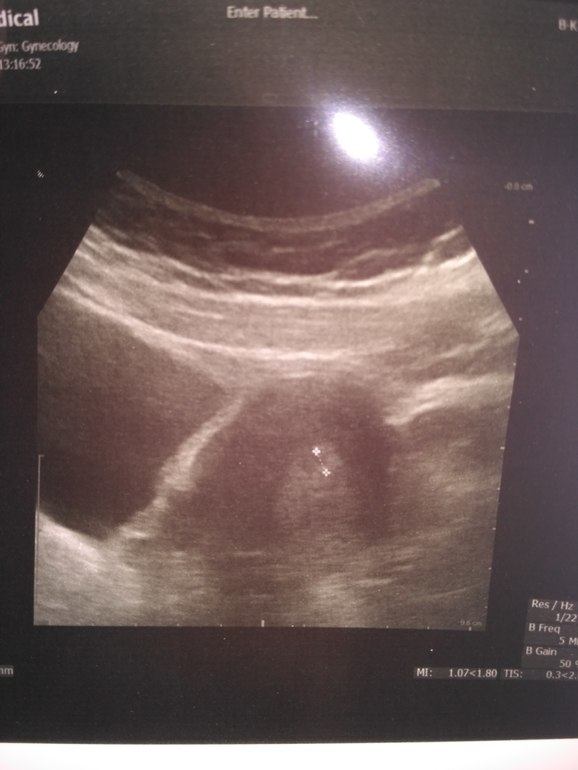

Анализы и процедуры. Помощь в расшифровке результатовВсем привет! У меня сегодня 19 ДПП, РЕ решила сделать УЗИ. Сначала водила по животику и сказала что она видит 2 ПЯ (была подсадка двух АА+АВ), куда подсаживали там и сидят, но один большой, а другой маленький (размеры не знаю). Решила сделать УЗИ вагинального, но там увидела только 1. В заключение РЕ написала одного... И сказала ждать УЗИ на СБ, возможно там появятся два сердечка... У кого такое было? Забилось два? Или одно?